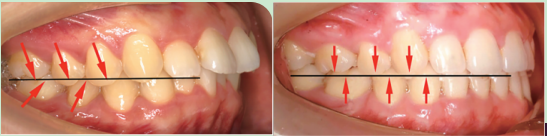

(1)上前牙内收的同时,还要压低。

上前牙内收,改善上颌前凸。上前牙内收时出现的直立通常会随之出现伸长,但是上前牙伸长,会使下颌不得不处于向后的位置,不利于改善颏部形态,因此要压低上前牙。

(4)下前牙充分直立,同时压低。

我们需要知道一个原则:牙齿移动的方向与骨骼移动的方向是相反的。如果下前牙唇倾,上下前牙的咬合会使下颌被迫处于后退位置。

只有下前牙充分内收,才能有下颌向前移动的空间。但是下前牙内收时,还要注意控制下前牙的高度,如果下前牙伸长,前牙的深覆合同样也会限制下颌的前伸移动,不利于改善高角骨性嘴凸下巴后缩。